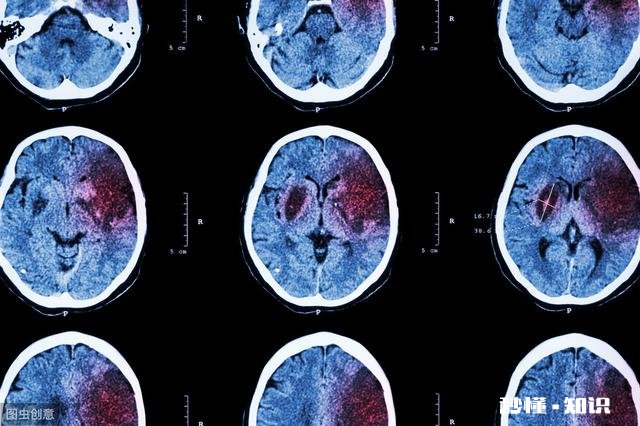

脑出血,又被称之为"脑溢血",因病情凶险,致残率高,死亡率高,被誉为中老年人的"健康杀手" 。

临床显示,脑出血多发于40-70岁的中老年人群 。病情一旦发作 , 极有可能因此丧命 。

经过检查,发现该男子的血压为220/120mmHg,CT结果显示左枕叶脑出血,必须即可进行手术 。

数据显示,临床约80%的脑出血,均与高血压有关 。

血压升高时,会导致脑内动脉破裂出血,得不到及时的救治 , 很有可能因此死亡 。